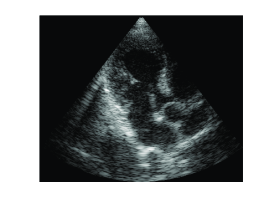

To demonstrate the equivalence of beamforming in time and frequency, we applied both methods on in vivo cardiac data yielding the images shown in Fig. 3. The imaging setup is that described in Section II-B with MHz. As can be readily seen, the images look identical.

(a)

(b)

A significant drawback of this method is its inability to restore weak reflectors. In the context of this approach they are treated as noise and are disregarded by the signal model. As a result, the speckle - granular pattern that can be seen in Fig. 3 - is lost. This severely degrades the value of the resulting images since information carried by speckle is of major importance in many medical imaging modalities. For example, in cardiac imaging, speckle tracking tools allow to analyze the motion of heart tissues and to track effectively myocardial deformations [21], [22].